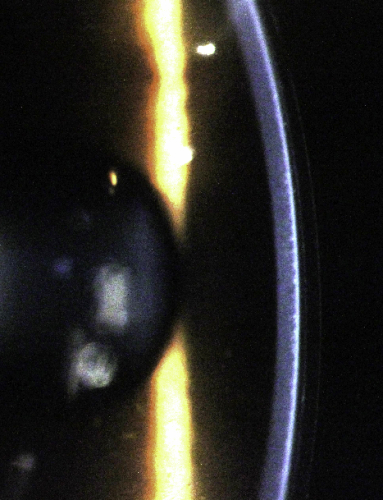

In these complex cases using topography-based lens design is a no-brainer for me. To marry the correct peripheral fit with the appropriate sagittal height and base curve for the desired refractive change with a trial lens would be time-consuming and inaccurate, even if such a post-LASIK hyperopic design set existed. Instead I plugged the patients topography into rigid lens simulation software EyeSpace (Innovatus Technology) and designed a custom hyperopic orthoK lens for each eye. Because the cornea is reasonably regular we can use a rotationally symmetrical lens to get a great fit. Of course with all hyperopic orthoK the lens base curve is steeper than the existing corneal curvature to create additional plus power.

EyeSpace simulation, post-lens tear profile and the real lens on the left eye. Note the slightly irregular central tear profile due to the LASIK result.